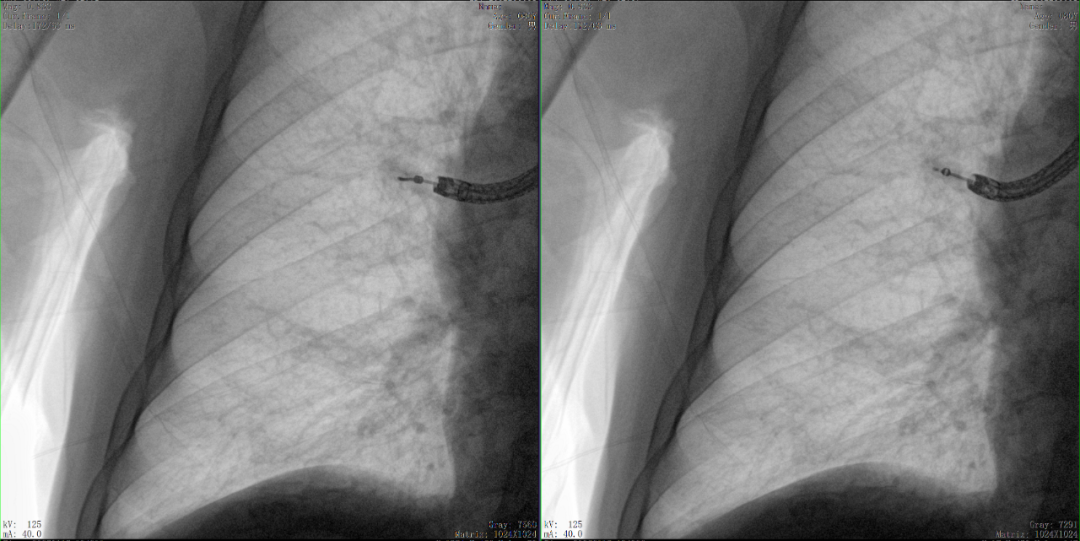

病例3:超聲支氣管鏡下肺活檢(80歲)

三維C形臂還可以創新性地應用在呼吸介入領域。例如,在經皮穿刺或經支氣管鏡肺結節活檢、定位、消融等場景中,用于確認工具是否到達病灶、消融范圍是否完全覆蓋病灶等。

二維影像無法準確判斷工具是否到達病灶

三維各切面影像都顯示工具達到病灶內